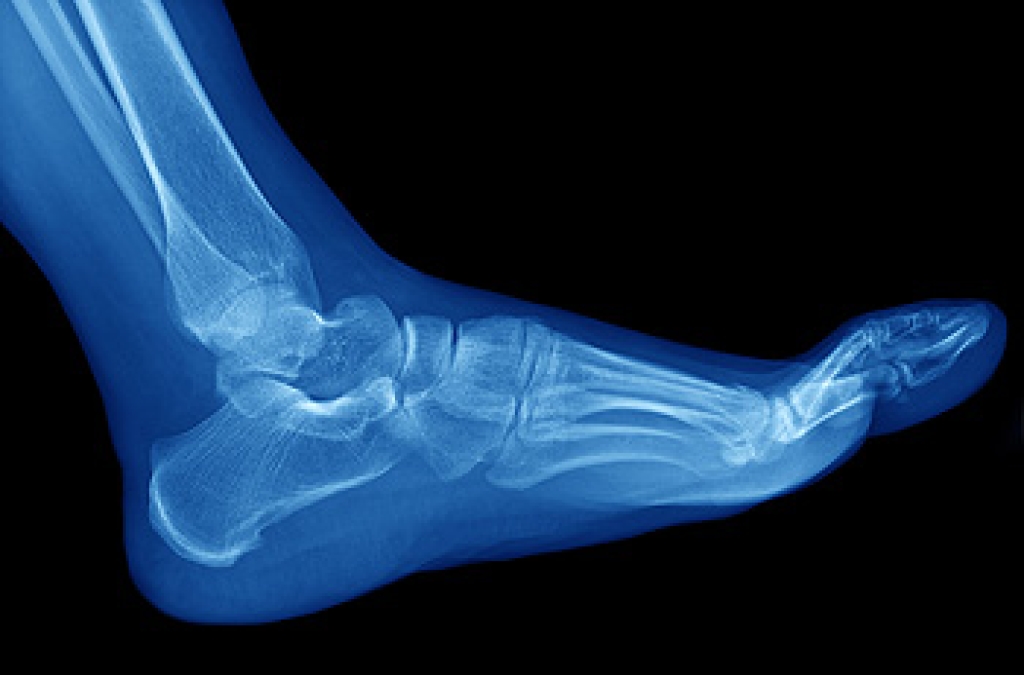

To increase performance and avoid the risk of injury, it is important to choose the right running shoe based on your foot type. The general design of running shoes revolves around pronation, which is how the ankle rolls from outside to inside when the foot strikes the ground.